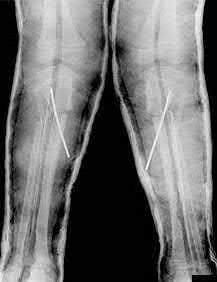

Question 20

A 3-year-old girl is evaluated for severe, progressive bilateral genu varum. Radiographs demonstrate medial metaphyseal beaking, fragmentation, and depression of the proximal medial tibial physis.

According to the Langenskiöld classification of infantile Blount's disease, at which stage does an overt physeal bony bar (epiphyseal-metaphyseal bridge) definitively form across the medial physis, conferring a high risk of recurrence without bar excision?

Explanation

The Langenskiöld classification describes progressive radiographic changes in infantile Blount disease. Stage I-IV show worsening metaphyseal beaking and stepping. Stage V shows a deep cleft separating the medial epiphysis into two portions. Stage VI is definitively characterized by the formation of a solid medial physeal bridge (bony bar) between the epiphysis and metaphysis, halting medial growth completely and often requiring bar resection along with osteotomy.